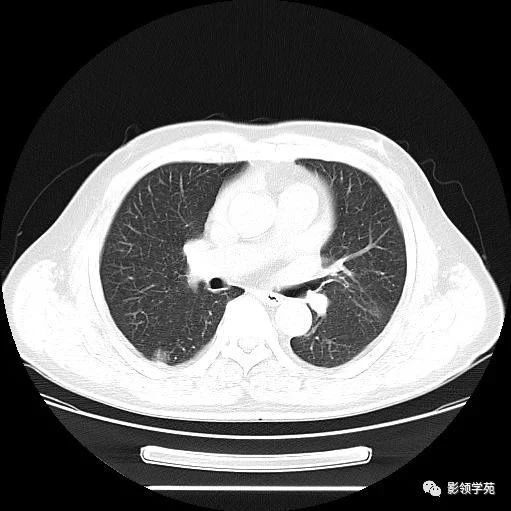

主因咳嗽1周,无发热——周围型肺癌 影领学苑 · 公众号 · · 5 年前 · |

肺部空洞病灶的影像诊断 影领学苑 · 公众号 · · 5 年前 · |